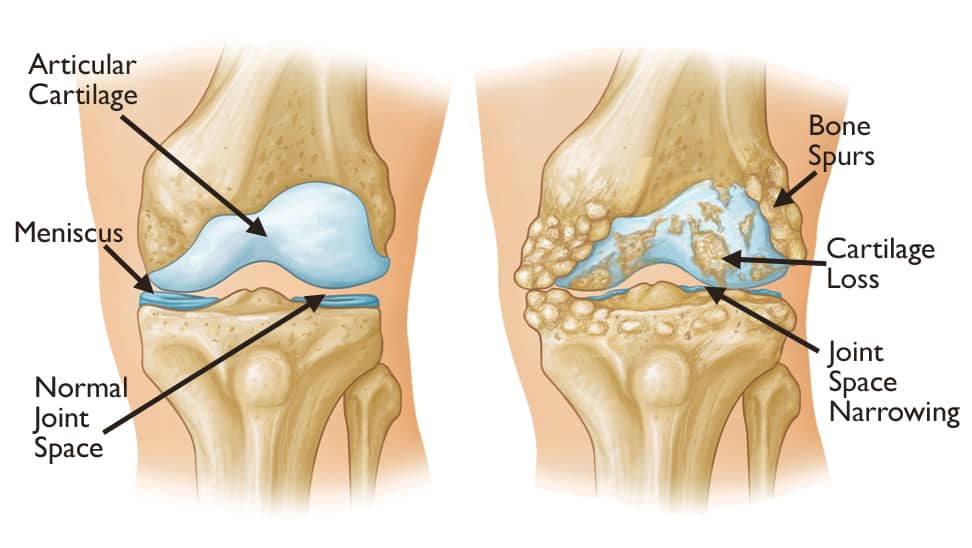

Cartilage. A smooth layer of cartilage covers the ends of bones in a joint. Cartilage cushions the bone and allows the joint to move easily without the friction that would occur with bone-on-bone contact.

The most common type of arthritis is osteoarthritis. Also known as wear and tear arthritis, osteoarthritis occurs when the cartilage that cushions and protects the ends of bones gradually wears away.

In many cases, bone growths called spurs develop at the edges of osteoarthritic joints. The bone can become harder (sclerosis). The joint becomes inflamed, causing pain and swelling. Continued use of the joint is painful.